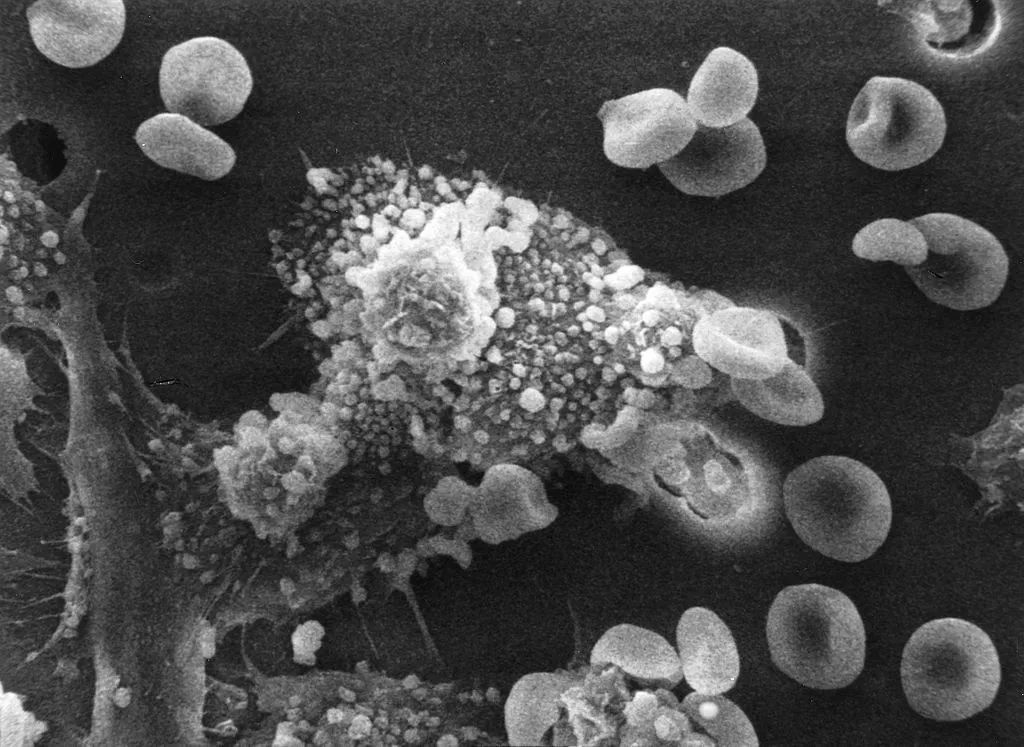

人类疱疹病毒的组织学切片显示受感染的细胞,包括细胞核和细胞质中的包涵体

不过,这些悄悄潜伏在人体内的病毒固然可怕。但自它们入侵人类身体的那天起,人体内的免疫系统就不停的加班加点。它们不断逮捕病原体,制造抗体来保护身体的细胞。所以,就算病毒潜伏再久,免疫系统给力也不容易生病,而且好得快。

比如最简单的方法就是保持良好的睡眠。这是因为我们体内的T细胞是负责对付癌细胞和病毒。若是得不到充足的睡眠,T细胞的数量就会减少,免疫系统就会下降,随之生病概率增加。此外,常做运动,也有利于我们增强免疫系统功能等。 不只是人类疱疹病毒这一大类,我们体内还可能长期潜伏着其他病毒或是致病细菌等。但它们的存在真的会对我们造成致命的威胁吗?其实不然。也许真正可怕的是人们根本不在乎,甚至去破坏体内那一辈子忠实保护自己的免疫大军。这样一来,那些致病因子又怎会对你手下留情呢?